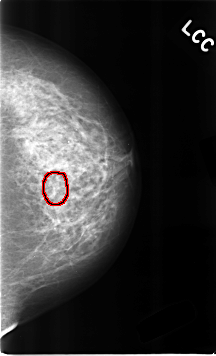

C_0310_1.LEFT_CC

FILE: C_0310_1.LEFT_CC.OVERLAY

TOTAL_ABNORMALITIES 1

ABNORMALITY 1

LESION_TYPE CALCIFICATION TYPE AMORPHOUS DISTRIBUTION CLUSTERED

ASSESSMENT 4

SUBTLETY 2

PATHOLOGY BENIGN

TOTAL_OUTLINES 1

BOUNDARY